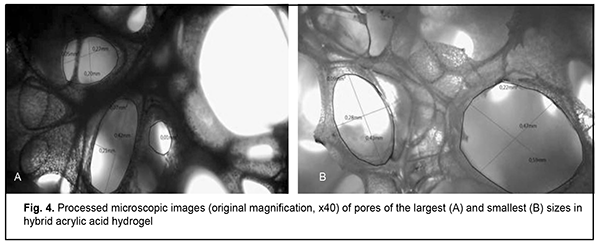

Porous structure of hydrogels Porosities of the high-density cross-linked hydrogel and low-density cross-linked hydrogel were 91.8%, and 95.0%, respectively, according to calculations based on formula (1). The calculated porosity of (poly) acrylic acid hydrogel composite was 85.9%. From optical microscopic evidence and electron microscopy evidence, the obtained hydrogels had a heterogeneous multilevel porous structure. That is, highest-level pores resulted also from coalescence of pore structures with a size that was two orders of magnitude lower. According to our calculations, the highest-level pores had a size of 120-180 ?m for the high-density cross-linked hydrogel and 460-670 ?m for the low-density cross-linked hydrogel (Fig. 3B).

The pore size in hybrid acrylic acid hydrogel composite varied from 200 ?m (Fig. 4A) to 590 ?m (Fig. 4B).